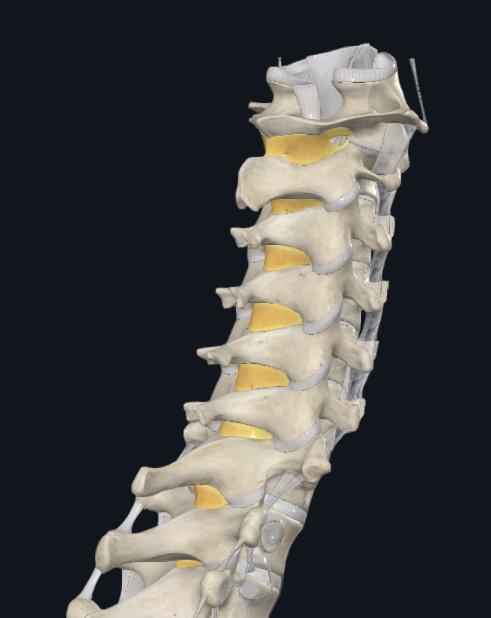

KYPHOPLASTY AND VERTEBROPLASTY

VertebralCompressionFractures(VCF)

While compression fractures can occur anywhere in the spine, they typically occur in the thoracic spine, and less commonly,lumbarspine

fracturescanoccuratmorethanonelevel,resultinginheightlossandkyphosis

Figure11:IllustrationofaVertebral CompressionFracture Figure12:EntrypointsandtrajectoriesoflowerthoracolumbarvertebralbodiesforPercutaneousVertebroplasty